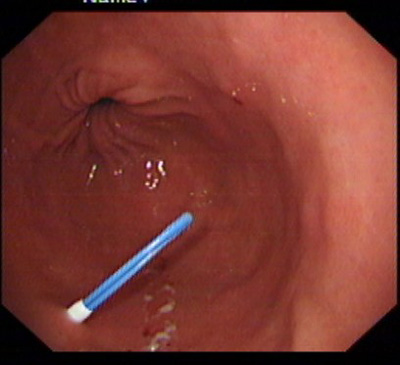

在消化科董蕾主任关心和指导下,消化科王进海教授,张利医师成功地给一位脑出血后吞咽困难的患者实施了经皮内镜下胃造瘘术。

该患者系男性,76岁,脑出血后留有吞咽困难后遗症,不能自主进食,需长期留置胃管供给营养,严重的影响了病人的生活质量和原发病的恢复。经皮内镜下胃造瘘术(Percutaneous endoscpic gastrostomy,PEG)是一种无需常规外科手术和全身麻醉的造瘘技术,可以在胃镜室或病房局麻下进行,因此是一种操作简便、创伤小、安全可靠的方法。该例患者在胃镜室局麻下进行手术,手术过程约10分钟,术后病人无明显不适,3天后即可从造瘘管给食物并出院。